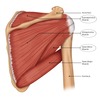

Label this image

what are the intrinsic shoulder muscles?

- deltoid

- teres major

- supraspinatus

- infraspinatus

- teres minor

- subscapularis